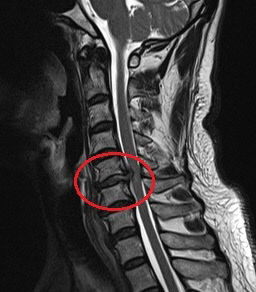

MRI 정밀 검사를 해 볼 필요가 있었다. 엑스레이만으로는 목의 정확한 상태를 알 수 없기 때문이다. 환자에게 MRI 검사의 필요성을 설명하고 검사를 해보니 경추부 추간판 탈출증 소견이 보였다. 흔히 얘기하는 목 디스크인 것이다.

목 디스크가 많이 돌출돼 신경근을 누르고 있으니 양어깨가 아프고 팔이 저리고 근력이 떨어질 수 밖에 없었다. 환자는 돌출된 디스크를 제거하고 위아래 목뼈를 안정적으로 고정시켜주는 ‘경추전방유합술’을 받고 수개월 동안 그를 괴롭히던 증상으로부터 자유로워질 수 있었다.

이 환자의 경우 거북목 자체가 원인이 아니라 경추의 퇴행성 질환으로 인한 신경근 압박이 주된 원인이었다. 그럼에도 거북목 치료만 받았으니 증상이 좋아질리 만무했다.